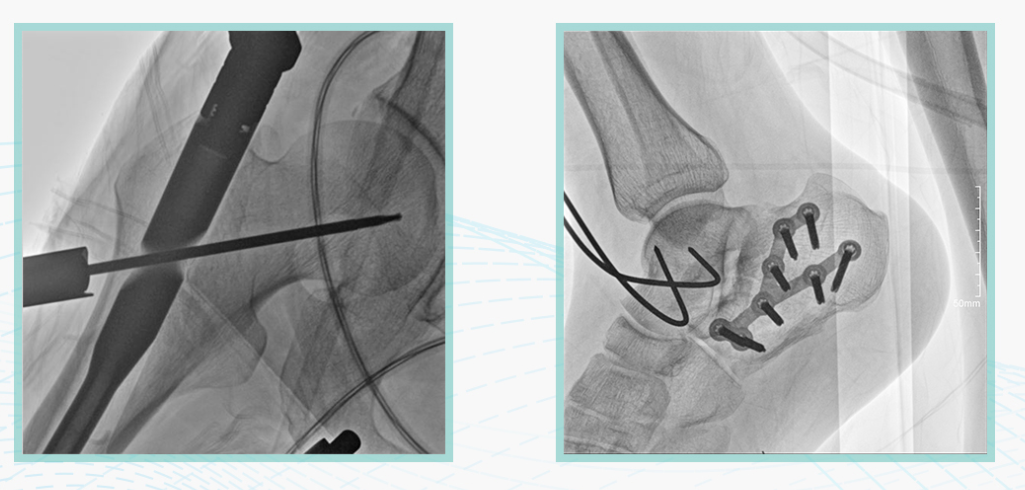

作为全球X线机的主要参与者,亿万28入口网页版-亿万28网页在线玩-万28官网下载最新版-亿万e网址pg-亿万28pg电子-亿万28赏金女王-亿万28娱乐科技在数字化X线产品线实现全线动态化之外,在移动C臂X光机产品线领域推出全新平板移动C臂产品:悦画。随着国家“千县工程”提升基层医疗卫生服务能力,外科对于手术介入引导设备的需求剧增。对于一台优秀的移动C臂X线机而言,如何保证最优质影像的同时,最大程度降低X线的辐射剂量,并在满足临床手术引导/定位的同时,最大程度的保护临床手术的医务人员,是悦画最为关切的问题。

亿万28入口网页版-亿万28网页在线玩-万28官网下载最新版-亿万e网址pg-亿万28pg电子-亿万28赏金女王-亿万28娱乐科技悦画移动C臂X线摄影系统,采用了业内技术最尖端的CMOS探测器。基于性能优异的针状CSI闪烁体涂层和高灵敏度的CMOS感光芯片,悦画可以实现在超低X线剂量条件下实现高清晰影像成像,相较于一般的影增移动C臂和平板C臂,动态范围更高,影像的层次感和对比度更好。

此外,骨科手术时间平均时长约为45分钟左右时间,长期的X线透视或摄影曝光剂量将对临床手术与操作医务工作者造成难以评估的健康风险,悦画通过支持摄影曝光参数的自主调节,可以保证在最低剂量水平下输出满足临床手术定位与引导所需要的影像质量,相较于市面上的固定曝光参数配置移动C臂,自主参数调节设计的曝光功能设计,可以大幅减少医务工作者的X线辐射剂量。

悦画在影像的伪影处理上,也积累多项图像处理专利技术。通过对植入物的精准识别,悦画能够精准祛除植入物伪影与运动伪影,保证高质量的影像输出,无论是影像的对比度、分辨率(清晰度)相较于市面上的移动C臂产品都更胜一筹。